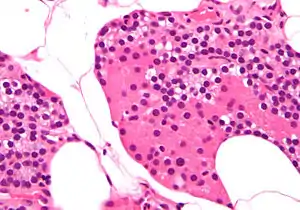

تسمى الغدد جارات الدرقية بهذا الاسم بسبب قربها من الغدة الدرقية - وتقوم بدور مختلف تمامًا عن الغدة الدرقية. يمكن تمييز الغدد جارات الدرقية بسهولة عن الغدة الدرقية حيث أنها تحتوي على خلايا مكتظة بكثافة، على النقيض من البنية الجُريبية للغدة الدرقية.[12] يوجد نوعان فريدان من الخلايا في الغدة الجار درقية:

- الخلايا الرئيسية الدريقية، تصنع وتفرز هرمون جار درقي. هذه الخلايا صغيرة، وتبدو داكنة عند امتلائخا بالهرمون الجار درقي، صافية عند إفراز الهرمون، أو في حالة الراحة.[13]

صورة مجهرية بتكبير عالٍ. صبغة الهيماتوكسيلين واليوزين. والخلايا الصغيرة الداكنة هي الخلايا الرئيسية الدريقية المسؤولة عن إفراز الهرمون الجار درقي.